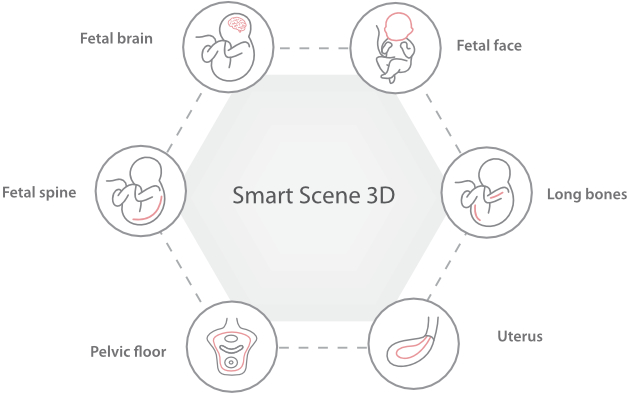

Full-stack Solution Powered by ZST?+

The ZST+ platform is an extraordinary innovation, representing an ultrasound evolution. Transforming ultrasound metrics from conventional beam-forming to channel data based processing. It overcomes the traditional trade-off limitation among spatial resolution, temporal resolution and tissue uniformity, delivering exceptional image quality for infinite imaging solutions with non-stop improvements.